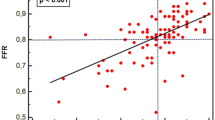

Compared with the iFR, the index value of the ICE-T was lower, the flow velocity was higher, and the intracoronary resistance was lower in all conditions where different coronary arteries were measured with or without hyperemia. The ADVISE study reported that the classification agreement (accuracy) between the iFR and the FFR was 94%; however, around the cut-off point for ischemic diagnosis, the iFR-FFR concordance rate was < 50%30. Our previous study findings indicated that the ICE-T is better than the iFR in terms of agreement with an ischemic diagnosis according to the FFR, although that study had a small sample size. In particular, the ICE-T had a higher concordance rate with the FFR for the diagnosis of ischemia in borderline cases such as the iFR adenosine zone (0.86 ≤ iFR ≤ 0.93; accuracy, overall; ICE-T 90%, iFR, 72.5%; adenosine zone; iFR 65%, ICE-T 80.0%)21. The usefulness of the IC-ECG in predicting microvascular obstruction in myocardial infarction31 and post-procedural myocardial injury in angina pectoris has also been reported32. These reports indicate that the local myocardial condition can be assessed sensitively using the IC-ECG. The combined use of pressure wire and the IC-ECG to assess myocardial ischemia and myocardial viability simultaneously may reduce the cost of cardiac magnetic resonance imaging and stress myocardial scintigraphy. The ICE-T requires a shorter analysis period than the iFR because it can selectively detect finer electrical potentials representing cardiac muscle activity near the tip of the pressure wire where the pressure sensor is located33. Therefore, the ICE-T measure might select an analysis interval with lower intracoronary resistance than the aortic pressure-dependent iFR measure regardless of the measurement conditions.